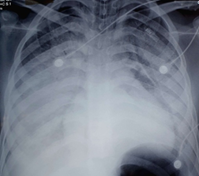

The chest X-ray revealed a diffuse bilateral alveolo-interstitial syndrome, filling both lung fields (Figure 2), in contrast to the initial chest X-ray (before methotrexate treatment), which was normal (Figure 1).

Figure 2: Chest X-ray on Day 5 of Treatment.